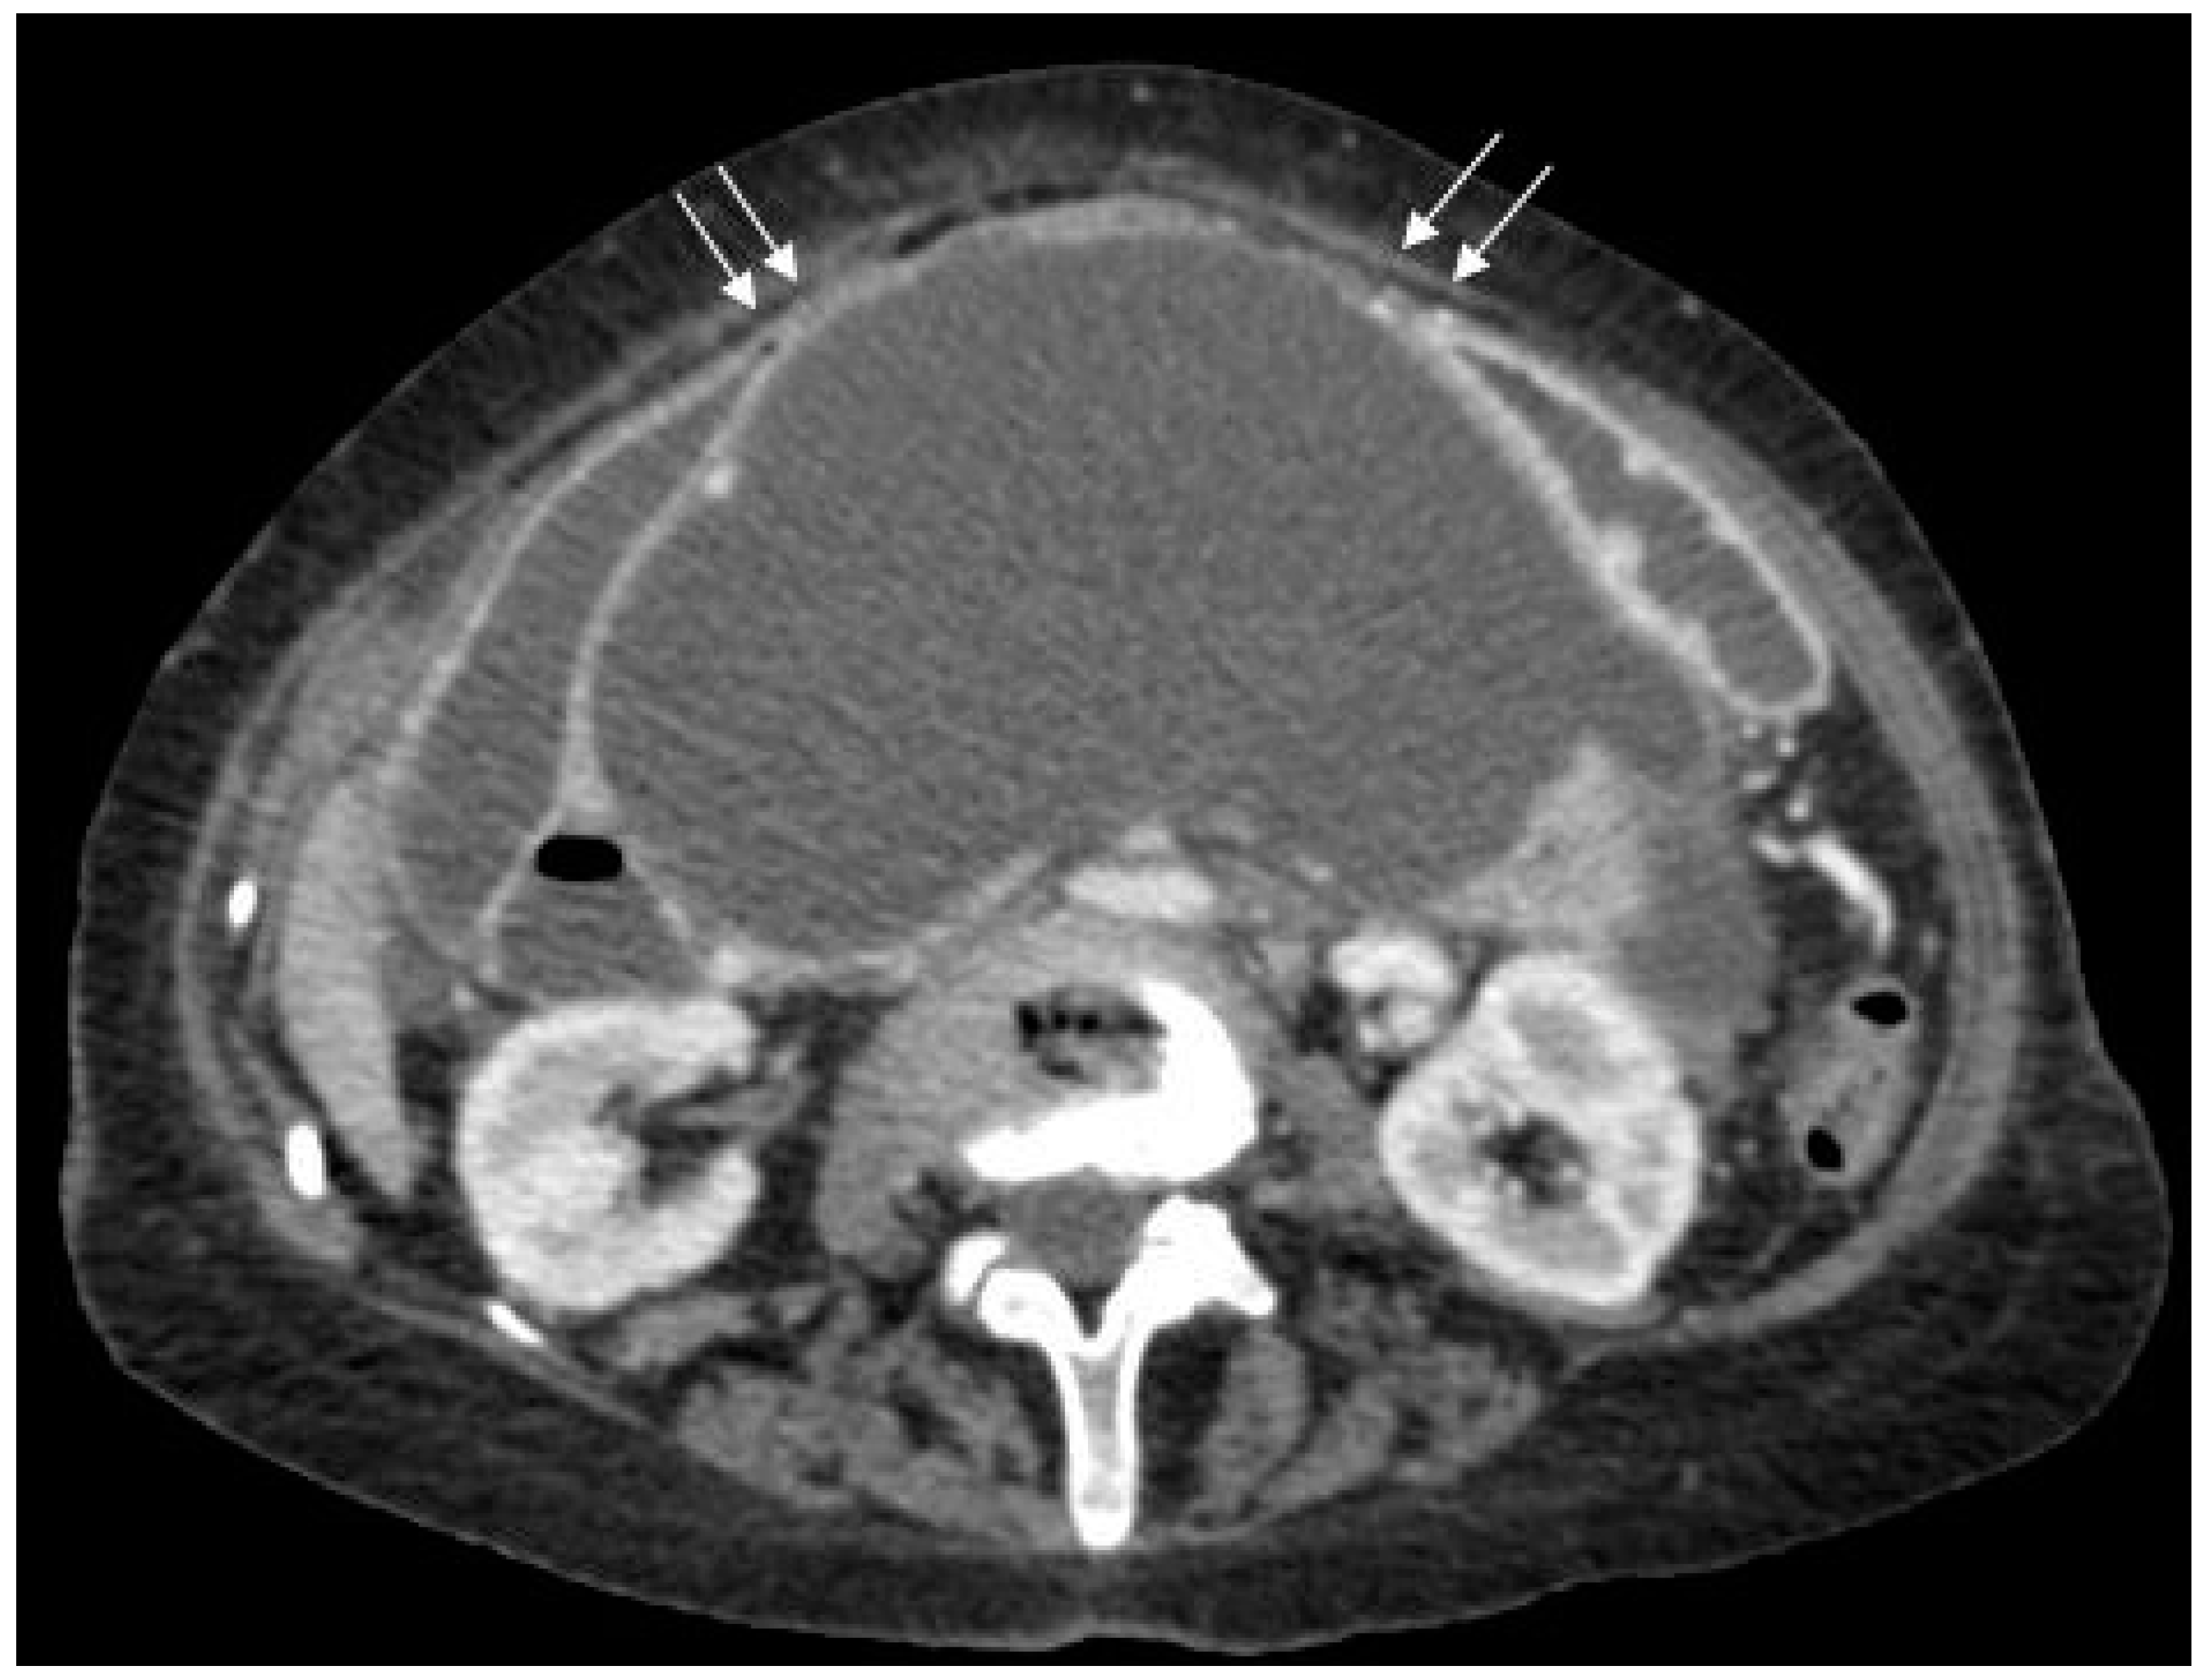

Figure 2.

Axial post-contrast CT scan of the upper abdomen showing the inferior aspect of the cyst with bi-lobed appearance (arrows) in the pelvis.